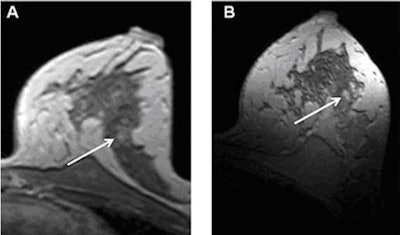

All patients were rescanned on a 1.5-tesla whole-body MRI system (Magnetom Espree, Siemens Healthcare) within 48 hours, using a standardized clinical protocol. Subtraction images were acquired at both 1.5-tesla and 7-tesla field strengths (shown below).

| T1-weighted postcontrast imaging of a 49-year-old woman; suspicious lesion in the lateral side of the breast at 1.5 tesla (A) and more clearly at 7 tesla (B). All images courtesy of Dr. Lale Umutlu. |